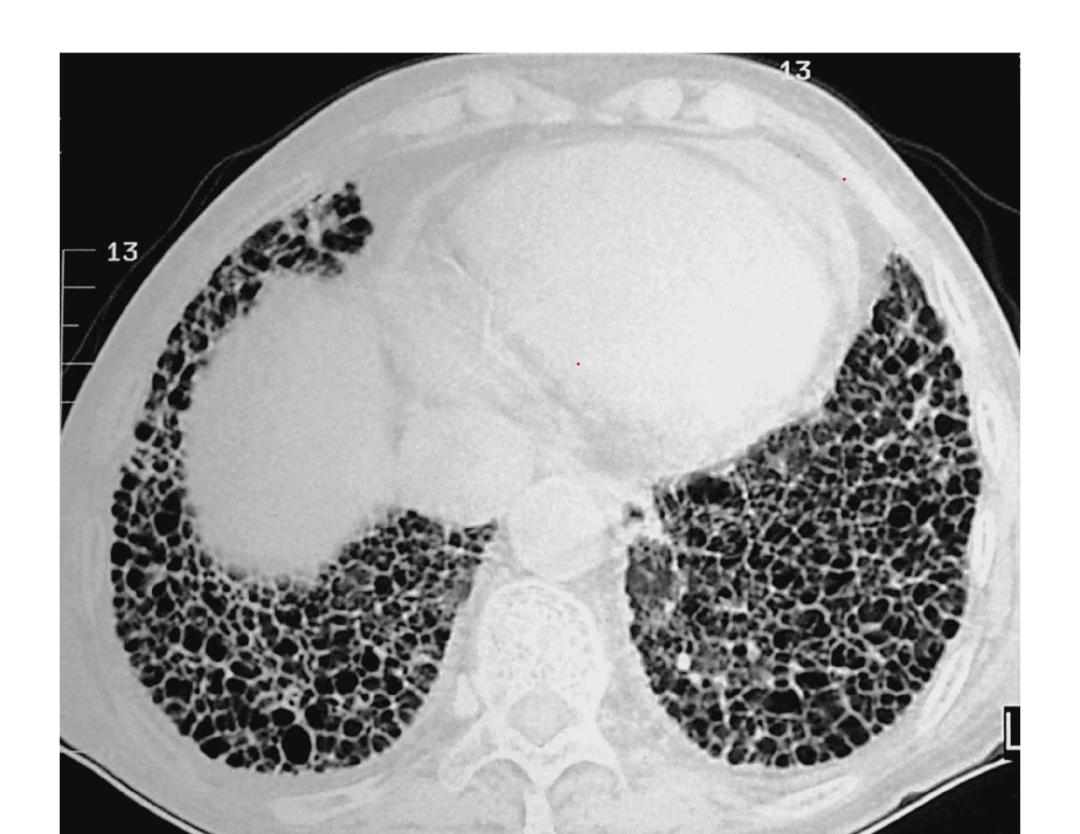

类风湿关节炎是一种自身免疫性炎性疾病,不仅会引起关节慢性疼痛,而且也会影响到其他的器官健康,最常见的就是影响肺部,很容易出现肺间质纤维化的问题,进而导致呼吸困难等不良的症状。

肺间质纤维化的病人往往会有顽固性的咳嗽和进行性的呼吸困难,会严重的影响生活质量。发现肺间质纤维化,首先要尽快的明确病因,这是因为纤维化是一大类异质性疾病,有的原因非常明确,比如有一类纤维化是跟吸烟相关,大家远离*草烟**不接触二手烟之后,病变会逐步的吸收,治疗主要是脱离环境,还有一些纤维化跟风湿免疫病相关,例如类风湿性关节炎、皮肌炎等,就需要很好地控制原发疾病,当原发疾病改善之后肺间质病变也会有吸收、会有改善,最难治疗的是特发性肺间质纤维化,这一类患者目前成熟的治疗药物比较少,目前常用包括尼达尼布、吡非尼酮药物。中医治疗也是非常好的选择,中药的汤药和中成药很多会有化痰散结、补肺益肾、纳气平喘的作用,很多肺间质纤维化的病人症状也会得到非常好的控制。肺间质纤维化病人的急性加重期,在这个过程中很多病人的病情会突然的进展导致呼吸衰竭,这种情况下要抗感染治疗,给予糖皮质激素的治疗抑制特异性的炎症的进展,同时有可能会使用呼吸机。